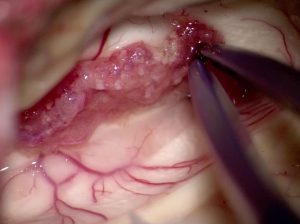

脈絡叢のビデオ2分(ここをクリック)

形や色や脳室壁への付着,動静脈の流入出など詳しくわかります)